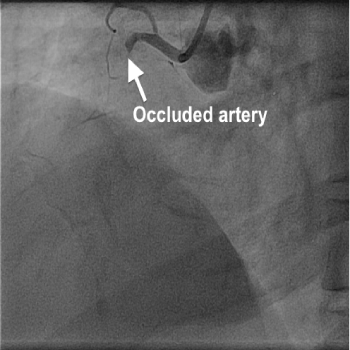

Her coronary angiogram, which was performed via right radial approach showed a totally blocked artery (right coronary artery) with plenty of thrombus, as expected. It was decided to perform angioplasty and therefore a wire was passed to cross the occlusion, which was successful. Then a thrombus aspiration catheter was inserted into the RCA, and a long serpentine clot was removed from the RCA. Further to this blood flow was established in the RCA, which showed a long segment of underlying narrowing of 70%. An OCT (optical coherence tomography) catheter was passed to assess the narrowing and size of the artery to decide about the stent. Then a drug coated stent was deployed in the narrowing to remove the block which was successful. This established a normal and brisk flow in the artery.